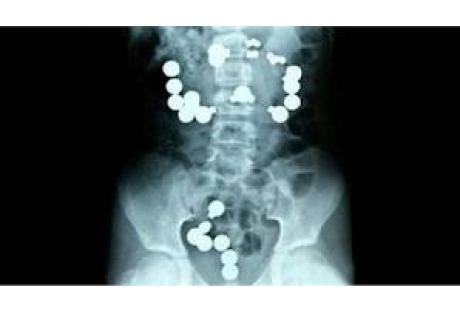

Με επιτυχία εγχειρίστηκε στη Ρωσία βρέφος 12 μηνών, το οποίο κατάπιε 42 μαγνητάκια ψυγείου.

Αμέσως πήγε το βρέφος στο νοσοκομείο, όπου σε υπέρηχο που του έκαναν οι ειδικοί φάνηκαν 42 μαγνητάκια στο πεπτικό του σύστημα.